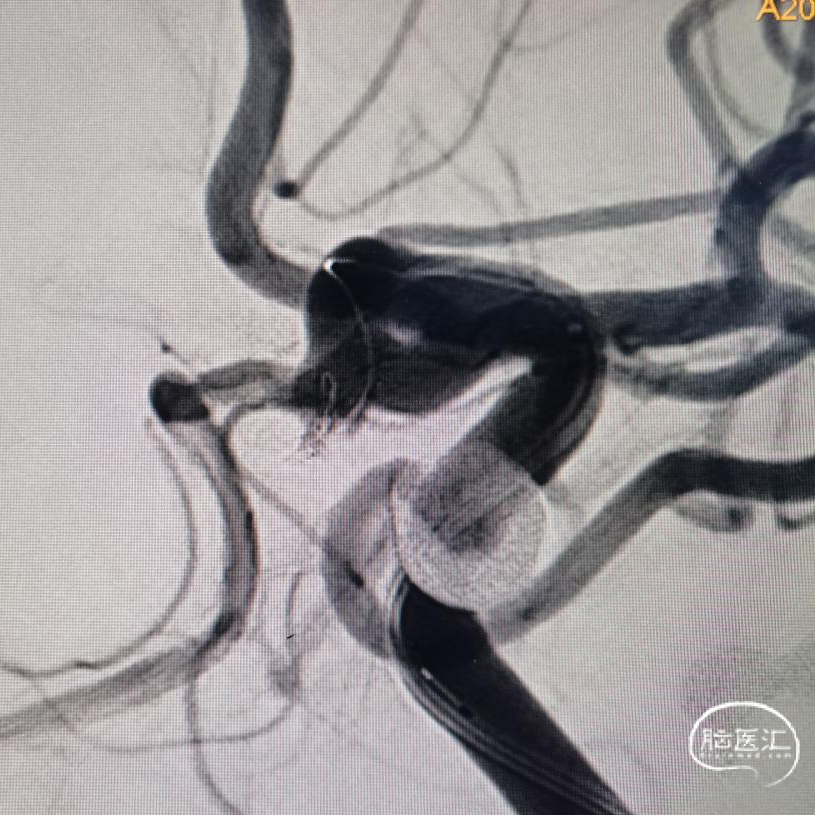

三米交换导丝,顺利到位。就看支架导管得了。既往有过顶破的经历,因此特别小心。好在三米支撑导丝的支撑能力比较好。但是也是一点一点的调整支架导管的位置,好在一切努力没有白费,支架导管一点一点越过后交通动脉起始,慢慢爬过过度弯曲之处。好在导管还能前行一些,紧绷的心终于放下了。起码离成功还有一半。于是就是弹簧圈微导管的到位,塑了个“猪尾”,第一次角度稍微大了一点点。如图。到位还算容易。也没有想太多,直接就用最小的圈,先把瘤填上,防止再次出血,可是现实并没有那么容易。

第一次